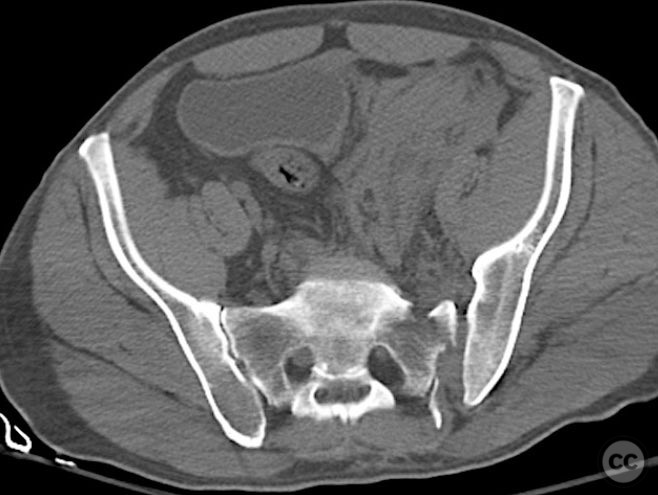

Pelvis - AO/OTA 6x